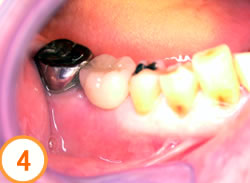

アバットメントを入れたところです

歯が入りました

セラミックの歯が入り良く噛めるようになりました